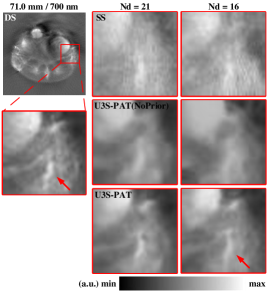

To further characterize the performance of U3S-PAT, we show the enlarged details of the images obtained using different methods in Fig.6. Upon observation of the magnified images, our U3S-PAT method exhibits superior structural visibility compared to both the SS method and U3S-PAT without prior embedding. Even at Nd=16, the quality of the U3S-PAT image remains unaffected, with only minor edge blurring observed in the region indicated by the red arrow. These findings highlight the effectiveness of the proposed self-supervised image reconstruction algorithm.

Next, we perform quantitative evaluation of the image reconstruction results. We use peak signal noise ratio (PSNR) and structural similarity (SSIM) for evaluation, and the obtained results are presented in Table I. At , the U3S-PAT results showed an average increase of 120.48 in PSNR and 34.31 in SSIM compared to the SS results. At ND=16, the PSNR increased by 106.15 and SSIM increased by 39.25 on average. This means that the intensity values obtained by the U3S-PAT method are closer to the reference DS image in both settings. In addition, when and , U3S-PAT improves PSNR by 18.87 and 19.89, and SSIM by 16.70 and 18.30, respectively, compared to the U3S-PAT (NoPrior) method. U3S-PAT method consistently achieves superior performance across all metrics when utilizing prior embedding.